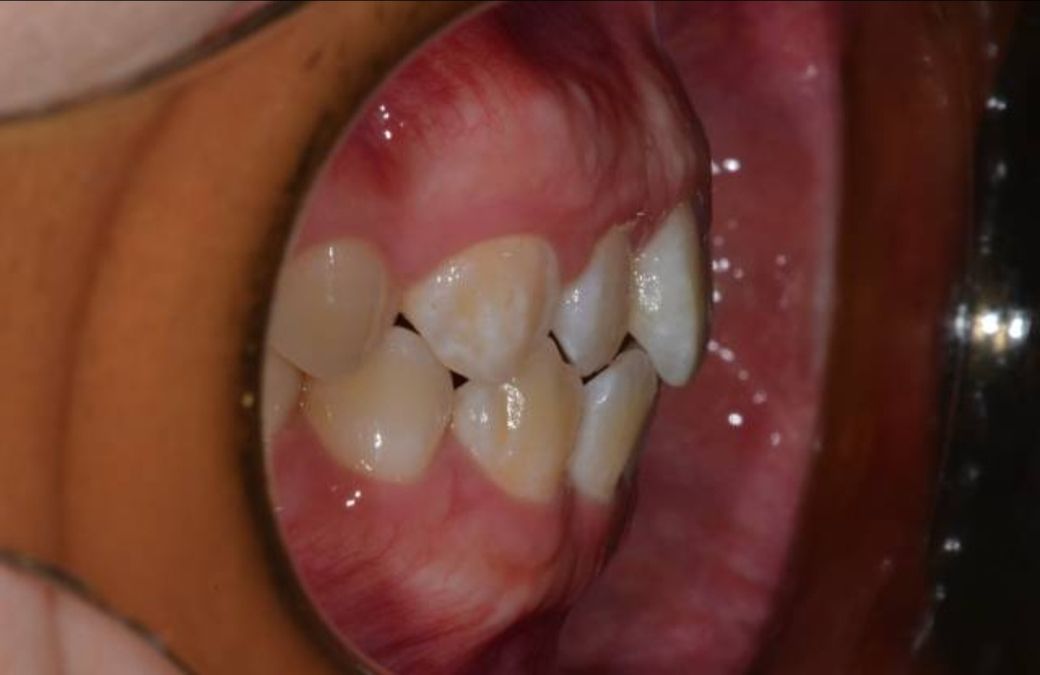

• 3번 째 사진

-긴민한것도 잇지만 오른쪽치아 쪽이 반대교합이 되고 있으니 교정을 상담해보세요.